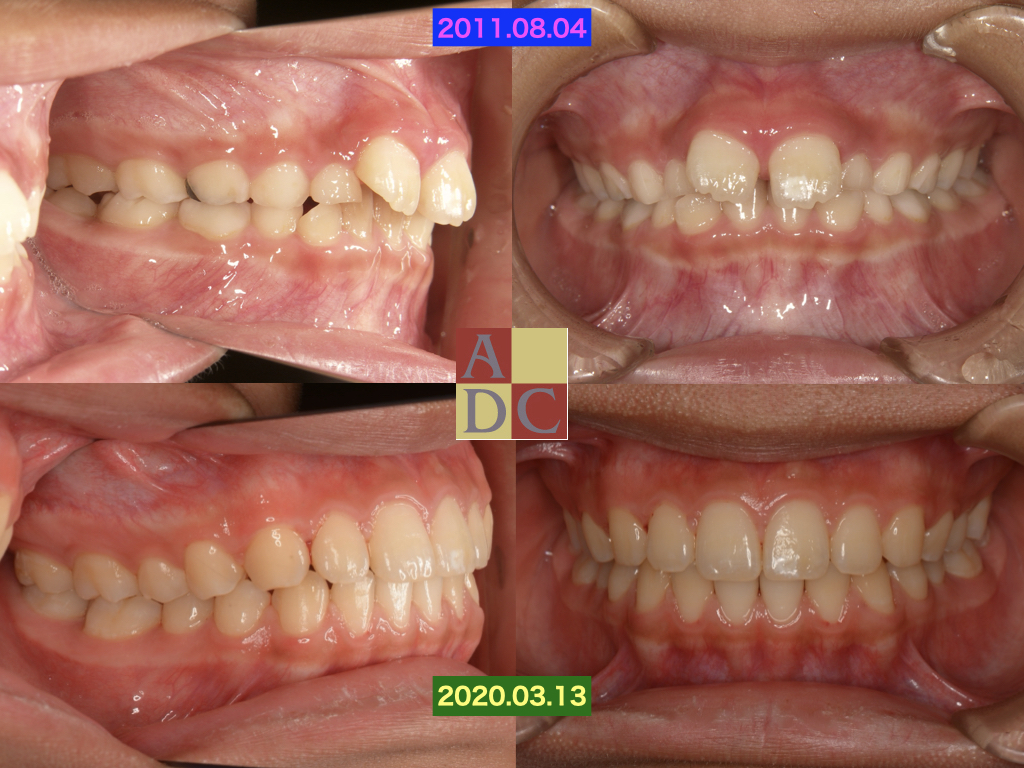

この子は紹介の子供

出っ歯だからどうにかしてほしいと、知人から・・・

放っておいたら、抜歯矯正か?外科矯正になっていたかも?

マイオブレースを使用し、非抜歯でブラケット無しで完了!!